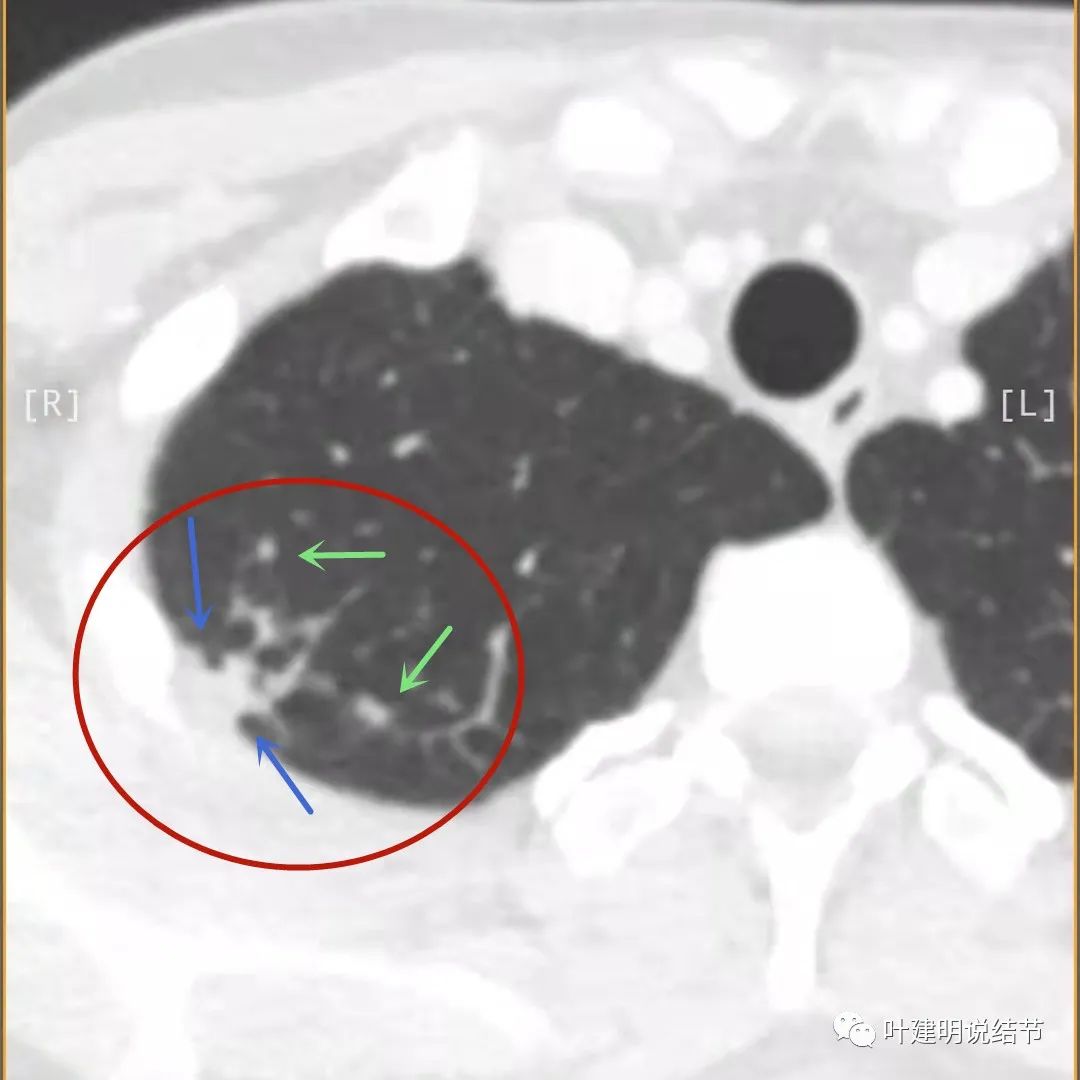

我们再来看薄层的CT图像:

病灶出现,模糊的磨玻璃影

部分密度过高,且呈条状

邻近胸膜有增厚(蓝色箭头),主病灶边界较清(红色箭头),实性部分密度过高(粉色箭头),旁边有磨玻璃影,散且模糊(砖色箭头)

邻近胸膜有增厚(蓝色箭头),主病灶实性部分密度过高(粉色箭头),旁边有磨玻璃影,散且模糊(砖色箭头)